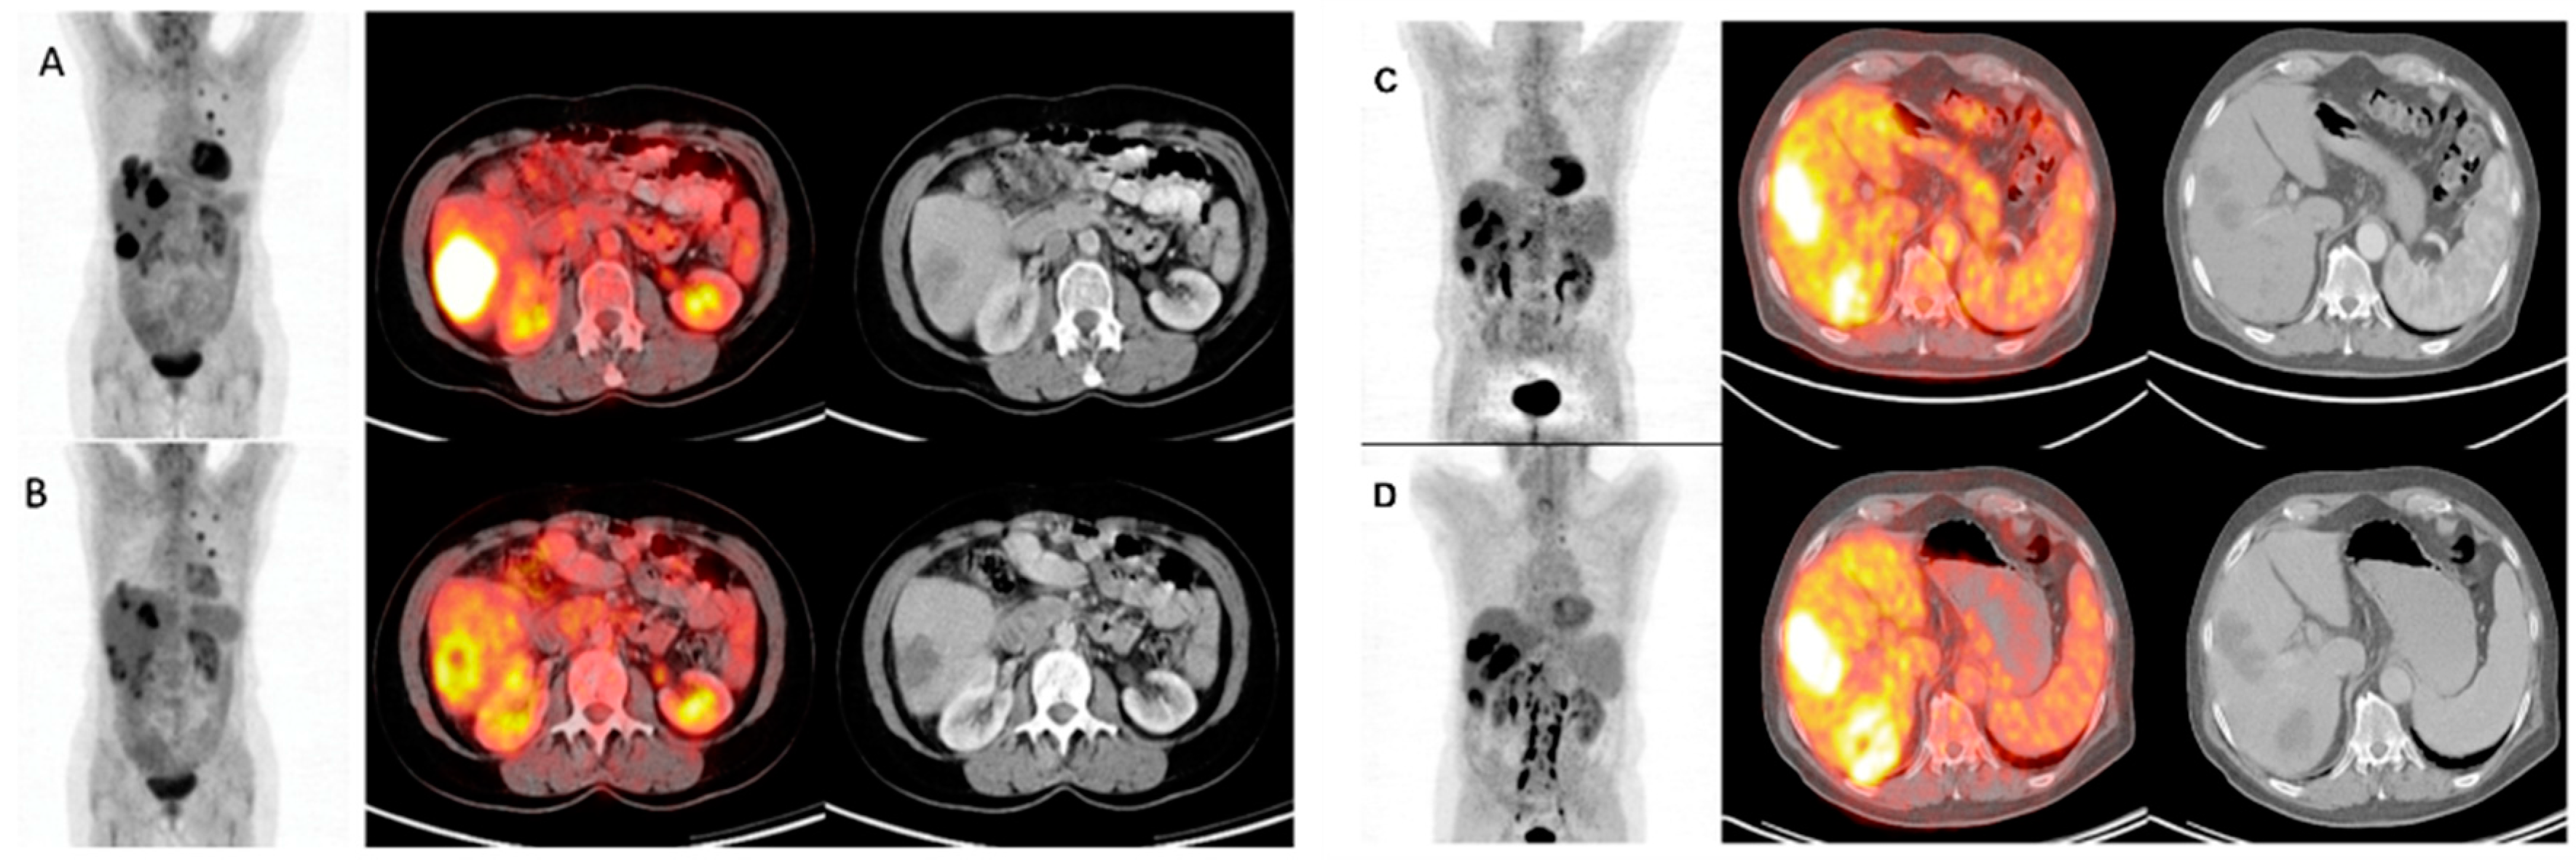

2.3. Metabolic Imaging with FDG-PET/CT

4. Hepatic Metastatic Disease

- Hendlisz, A.; Golfinopoulos, V.; Garcia, C.; Covas, A.; Emonts, P.; Ameye, L. Serial FDG–PET/CT for early outcome prediction in patients with metastatic colorectal cancer undergoing chemotherapy. Ann. Oncol. 2012, 23, 1687–1693. [Google Scholar] [CrossRef] [PubMed]

- Hendlisz, A.; Deleporte, A.; Delaunoit, T.; Maréchal, R.; Peeters, M.; Holbrechts, S.; van den Eynde, M.; Houbiers, G.; Filleul, B.; van Laethem, J.L.; et al. The prognostic significance of metabolic response heterogeneity in metastatic colorectal cancer. PLoS ONE 2015, 10, e0138341. [Google Scholar] [CrossRef] [PubMed]